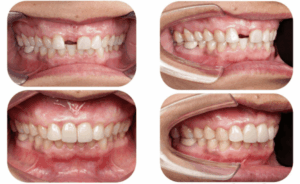

A dental implant is a titanium post placed into the jawbone to replace the root of a missing tooth. Once healed, it supports a crown, bridge, or denture, restoring natural function and aesthetics.

Studio Dentale focuses on combining safety, precision, and aesthetics in every implant case.

Studio Dentale is a modern dental clinic in Kathmandu offering advanced implant dentistry with a patient-centered approach.

- Focus on long-term function and aesthetics